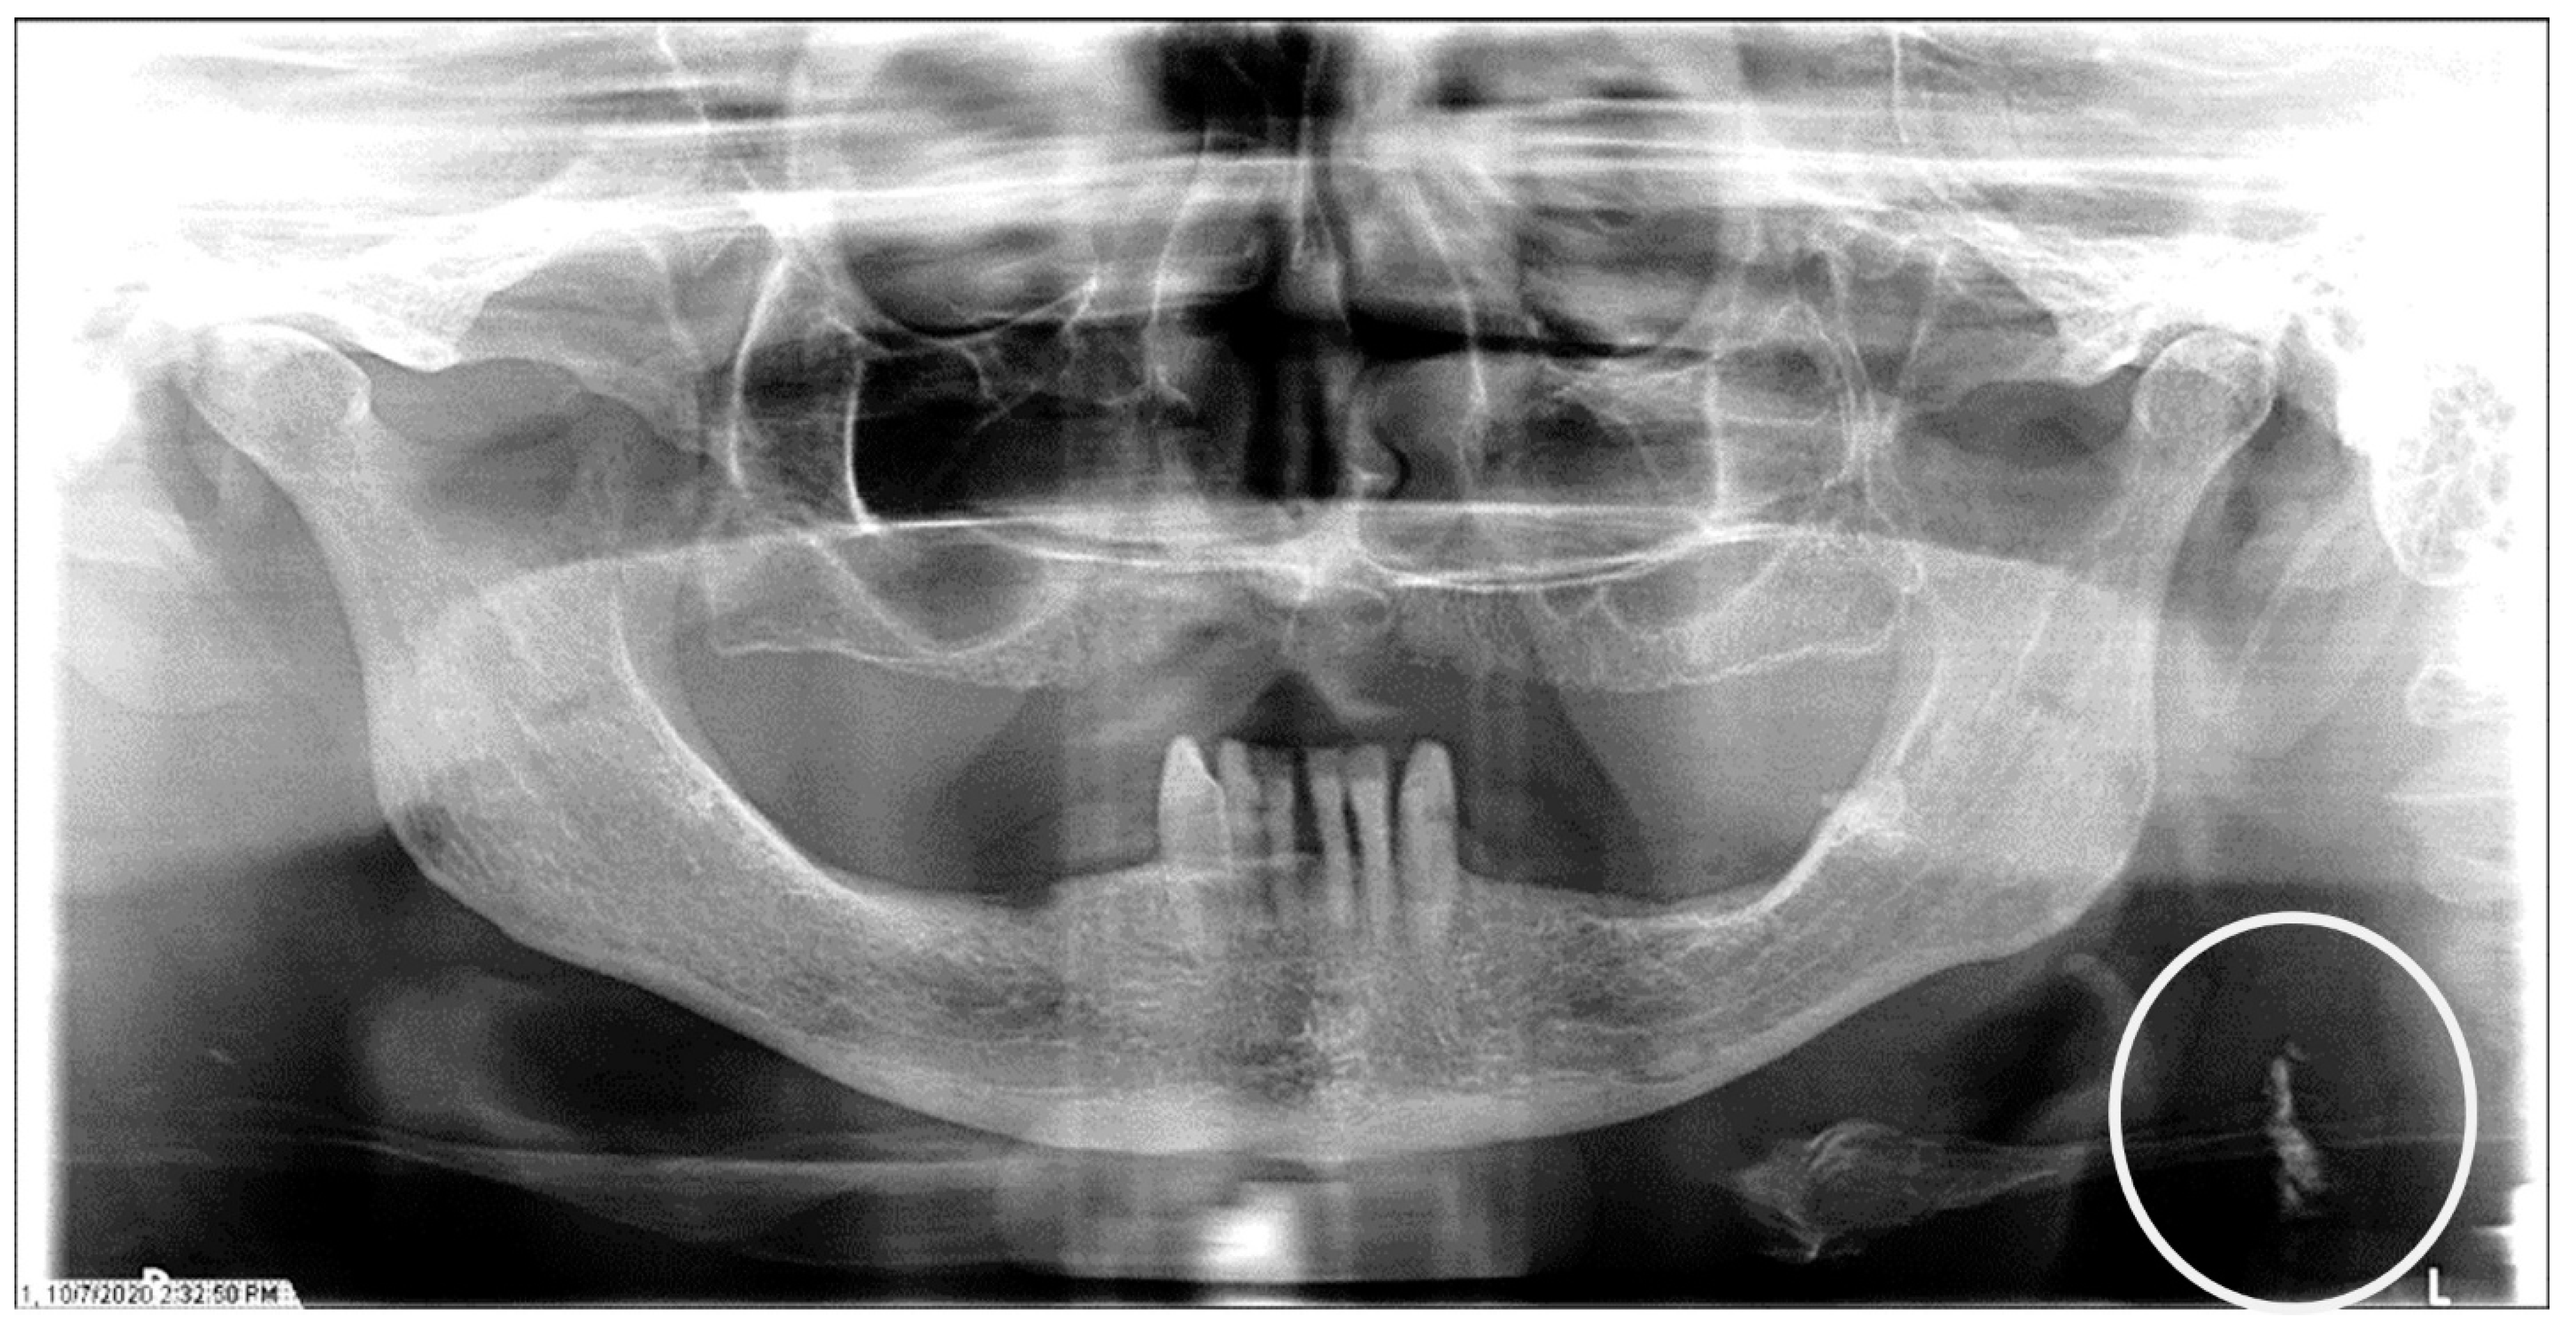

The characteristics of the CAC patients are presented in Table 1. Between 2014 and 2023, there were 559 patient records with the terms “carotid artery calcification” or “carotid” or “calcification of the carotid artery” noted. After the panoramic radiographs were reviewed, 314 patients were confirmed to have a diagnosis of CAC (including 26 patients with a history of carotid endarterectomy). The remaining 245 patient records were excluded because of the absence of detectable CAC on PRs and the absence of PRs to review. The ages ranged from 29 to 92 years, with a median of 68 years. CAC was most prevalent (39.5%) in the seventh decade of life. There were 168 (53.5%) female and 146 (46.5%) male patients. The median age of the female patients was 68 years, and the median age of the male patients was 69.5 years. The calcifications were identified unilaterally in 168 (53.5%) patients (88 females/80 males; mean age: 67.8 years) (Figure 1 and Figure 2) and bilaterally in 146 (46.5%) patients (80 females/66 males; mean age: 68.6 years) (Figure 3, Figure 4 and Figure 5). The DMFT index in the CAC patients ranged from 8 to 32 (mean = 26.6). The frequency of patients with CAC with a history of hypertension, hyperlipidemia, diabetes mellitus, CVA, and CAD was 86.2%, 57.6%, 30.7%, 15.5%, and 28.7%, respectively.

Figure 2.

The panoramic radiograph of a 77-year-old female patient with a medical history of hypertension, hyperlipidemia, diabetes mellitus, and coronary artery disease showing a unilateral left carotid artery calcification (CAC) during a comprehensive dental examination. The CAC is encircled by a white line.